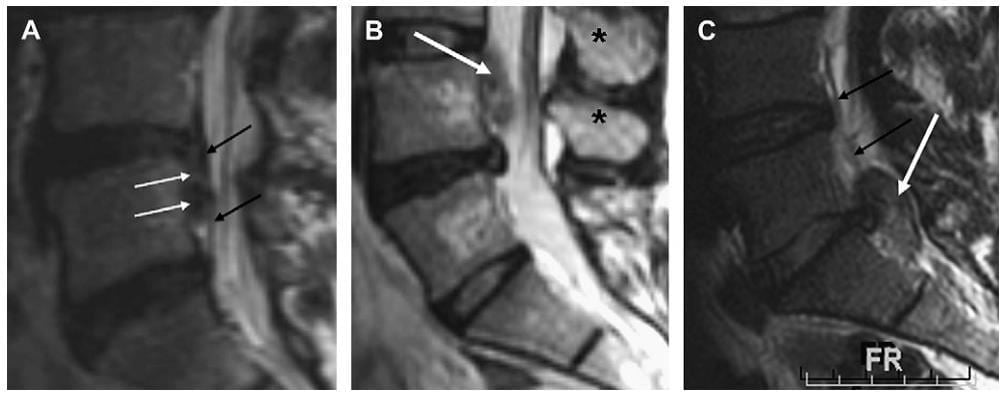

Thoát vị đĩa đệm cũng được phân loại theo mức độ lan. Độ lan được xem là tình trạng của vòng xơ bao quanh nhân đĩa. N ếu vòng xơ ngoài còn nguyên, thoát vị đĩa đệm được phân loại là kiểu được giới hạn và không có bất kỳ một sự thong thương nào với khoang ngoài màng cứng hoặc ống sống. Ví dụ, nếu tiêm thuốc cản quang iode vào phần thoát vị được giới hạn thì nó sẽ không rò vào khoang ngoài màng cứng hoặc ống sống từ chỗ khuyết trong vòng xơ. Các mô tả khác của thoát vị đĩa đệm là làm rõ mối tương quan của nó với dây chằng dọc sau. Trong sơ đồ mô tả này, các loại thoát vị đĩa đệm có thể chia thành duới dây chằng, xuyên dây chằng hoặc ngoài dây chằng phụ thuộc vào thoát vị đĩa đệm nằm trước dây chằng, lan qua dây chằng dọc sau hoặc thoát vị vào một vùng không được bao bọc dây chằng dọc sau ở phía sau (Hình 8). Mặc dù sơ đồ mô tả này có tác dụng để định vị thoát vị khi dây chằng dọc sau được nhìn thấy rõ, nhưng khó phân biệt được dây chằng dọc sau với các sợi ngoài của vòng xơ hoặc với màng cứng. Mối quan hệ của đĩa đệm với dây chằng dọc au chủ yếu phụ thuộc vào bất thường trên hình sagittal. Dây chằng dọc sau bám trực tiếp ở bờ sau thân sống phía trung tâm, ở đó không có một khoang nào cả. Dây chằng dọc sau bị hẹp lại ở cạnh trung tâm và không bám chắt với phần sau của thân sống vì vậy tạo ra một khoang gọi là khoang ngoài màng cứng phía trước. Khoang này là một vị trí giải phẫu quan trọng để nhận diện vì các mảnh đĩa đệm thường bị nhốt trong khoang ngoài màng cứng phía trước (Hình 8).

Hình 8. Sagittal T2W thắt lưnh cùng ở các bệnh nhân khác nhau minh hoạ nhiều loại thoát vị đĩa đệm. (A) thoát vị đĩa đệ lan xuống duới từ gốc ở đĩa đệm L4-L5 (mũi tên trắng) và nằm ngay trước dây chằng dọc sau (mũi tên đen) trong khoang ngoài màng cứng phía trước. Extrusion đĩa đệm (mũi tên trắng) nằm ở đường giữa (ghi nhận mỏm gai chỉ ra bằng các dấu sao đen) và ngay phía sau dây chằng dọc sau, không thấy rõ trên hình đường giữa vì dính trực tiếp vớiphần sau thân sống. Thoát vị đĩa đệm được xác định là lan vào trong ống sốngxuyên qua dây chằng dọc sau (thoát vị xuyên dây chằng). (C) thoát vị đĩa đệmthấy phía sau dây chằng dọc sau (mũi tên đen) và bắt nguồn ở ngay phía bên của dây chằng dọc sau. Dây có thể gọi là thoát vị ngoài dây chằng.